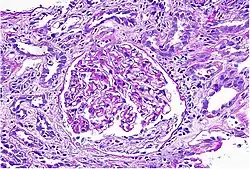

| Acute interstitial nephritis on light microscopy | |

While non-invasive patient evaluation (physical examination, blood and urine testing, imaging studies) can be suggestive, the only way to definitively diagnosis interstitial nephritis is with a tissue diagnosis obtained by kidney biopsy. Pathologic examination will reveal the presence of interstitial edema and inflammatory infiltration with various white blood cells, including neutrophils, eosinophils, and lymphocytes. Generally, blood vessels and glomeruli are not affected. Electron microscopy shows mitochondrial damage in the tubular epithelial cells, vacuoles in the cytoplasm, and enlarged endoplasmic reticulum.[23]